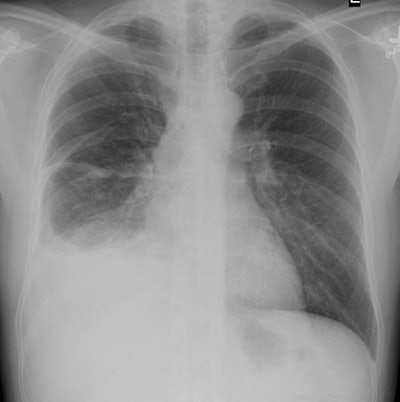

CXR: The lesion usually appears as a markedly thickened, nodular, irregular pleural based mass which coats the pleural surface and grows along fissures. The tumor often encircles the involved lung and is only rarely bilateral. Diffuse pleural thickening can be seen in 60% of cases or pleural masses in 45-60% [15]. Chest wall, diaphragmatic, and mediastinal invasion can be seen with more advanced disease. Contralateral asbestos related pleural disease is seen in 25-50% of cases. A moderate to large, ipsilateral pleural effusion is seen in 50-75% of cases. Because mesothelioma encases the lung it may fix the affected hemithorax so there is no shift away from the side of the tumor, in fact there may be evidence of volume loss on the affected side even in the presence of massive effusion.

Mesothelioma on CXR: Middle aged male presented with chest pain and shortness of breath. CXR demonstrated a moderate to large sized right pleural effusion abnormal nodular thickening of the pleura- particularly evident along the fissures. The patient had no known history of asbestos exposure. |